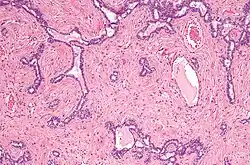

Seção vertical do testículo, para mostrar o arranjo dos dutos. -

Micrografia do rete testis envolvida por seminoma. Mancha de H&E. -